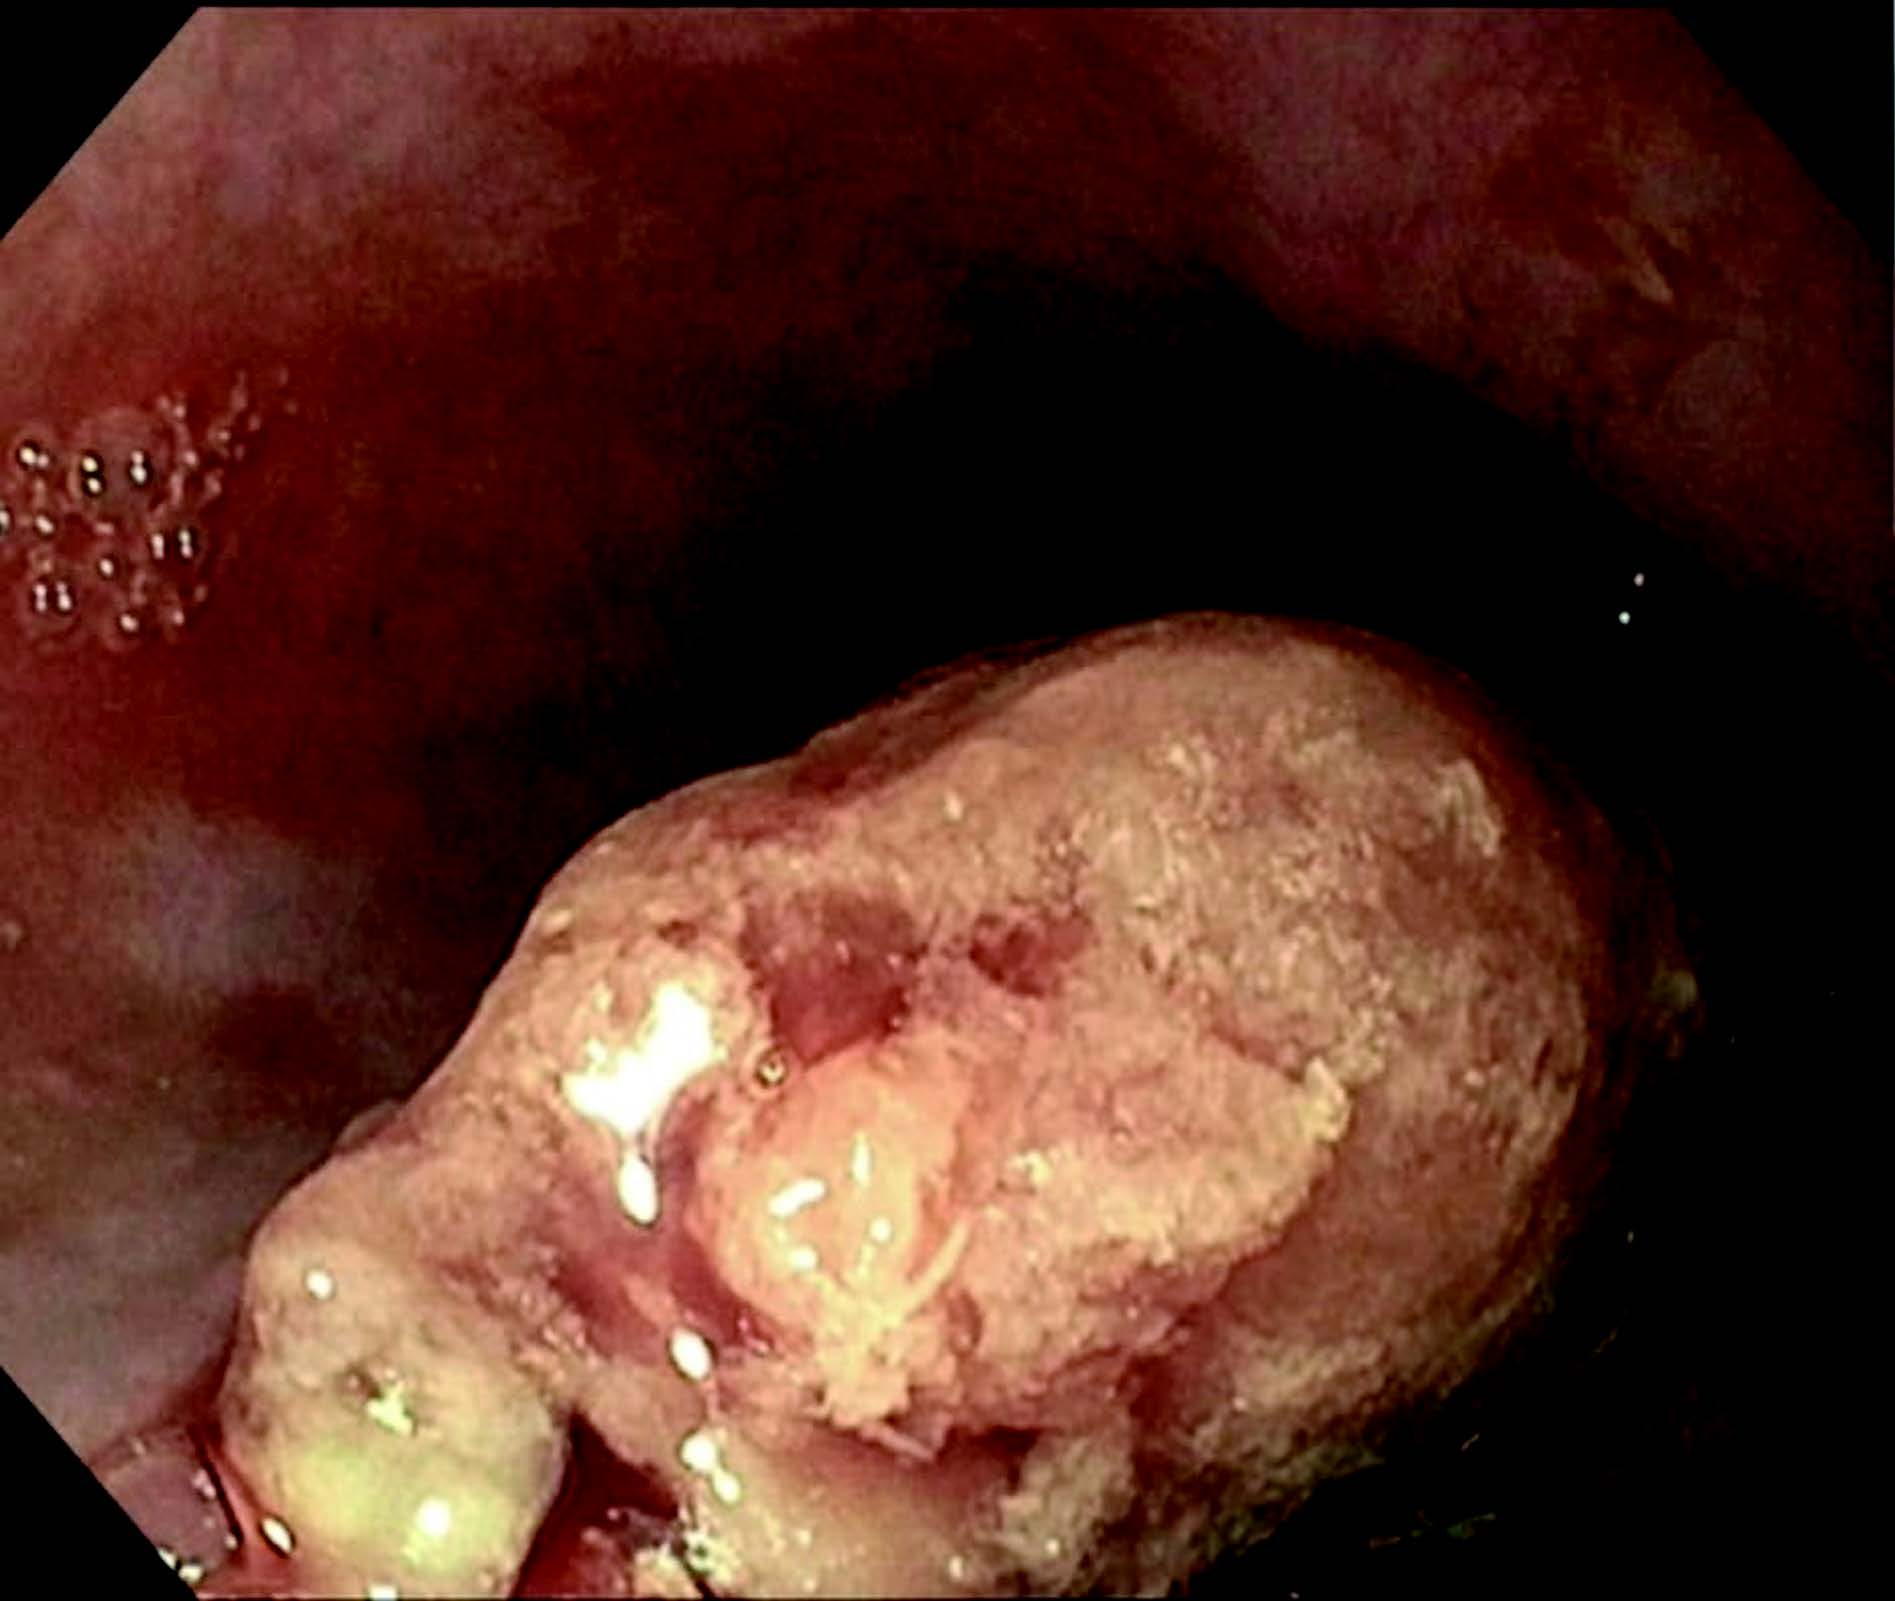

Bildequiz